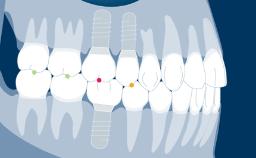

Design of all implant prostheses should be based on a prosthodontic plan and should address all specific planning factors identified as relevant.

There are a number of aspects that are common to the design of most implant fixed dental prostheses (or FDPs), and it is helpful to arrange these points in a logical design sequence.

The first point is selection of the type and configuration of the FDP. The next point is selection of the retention method, followed by consideration of the external aspects and internal structure required to address factors such as esthetics, function, and strength.